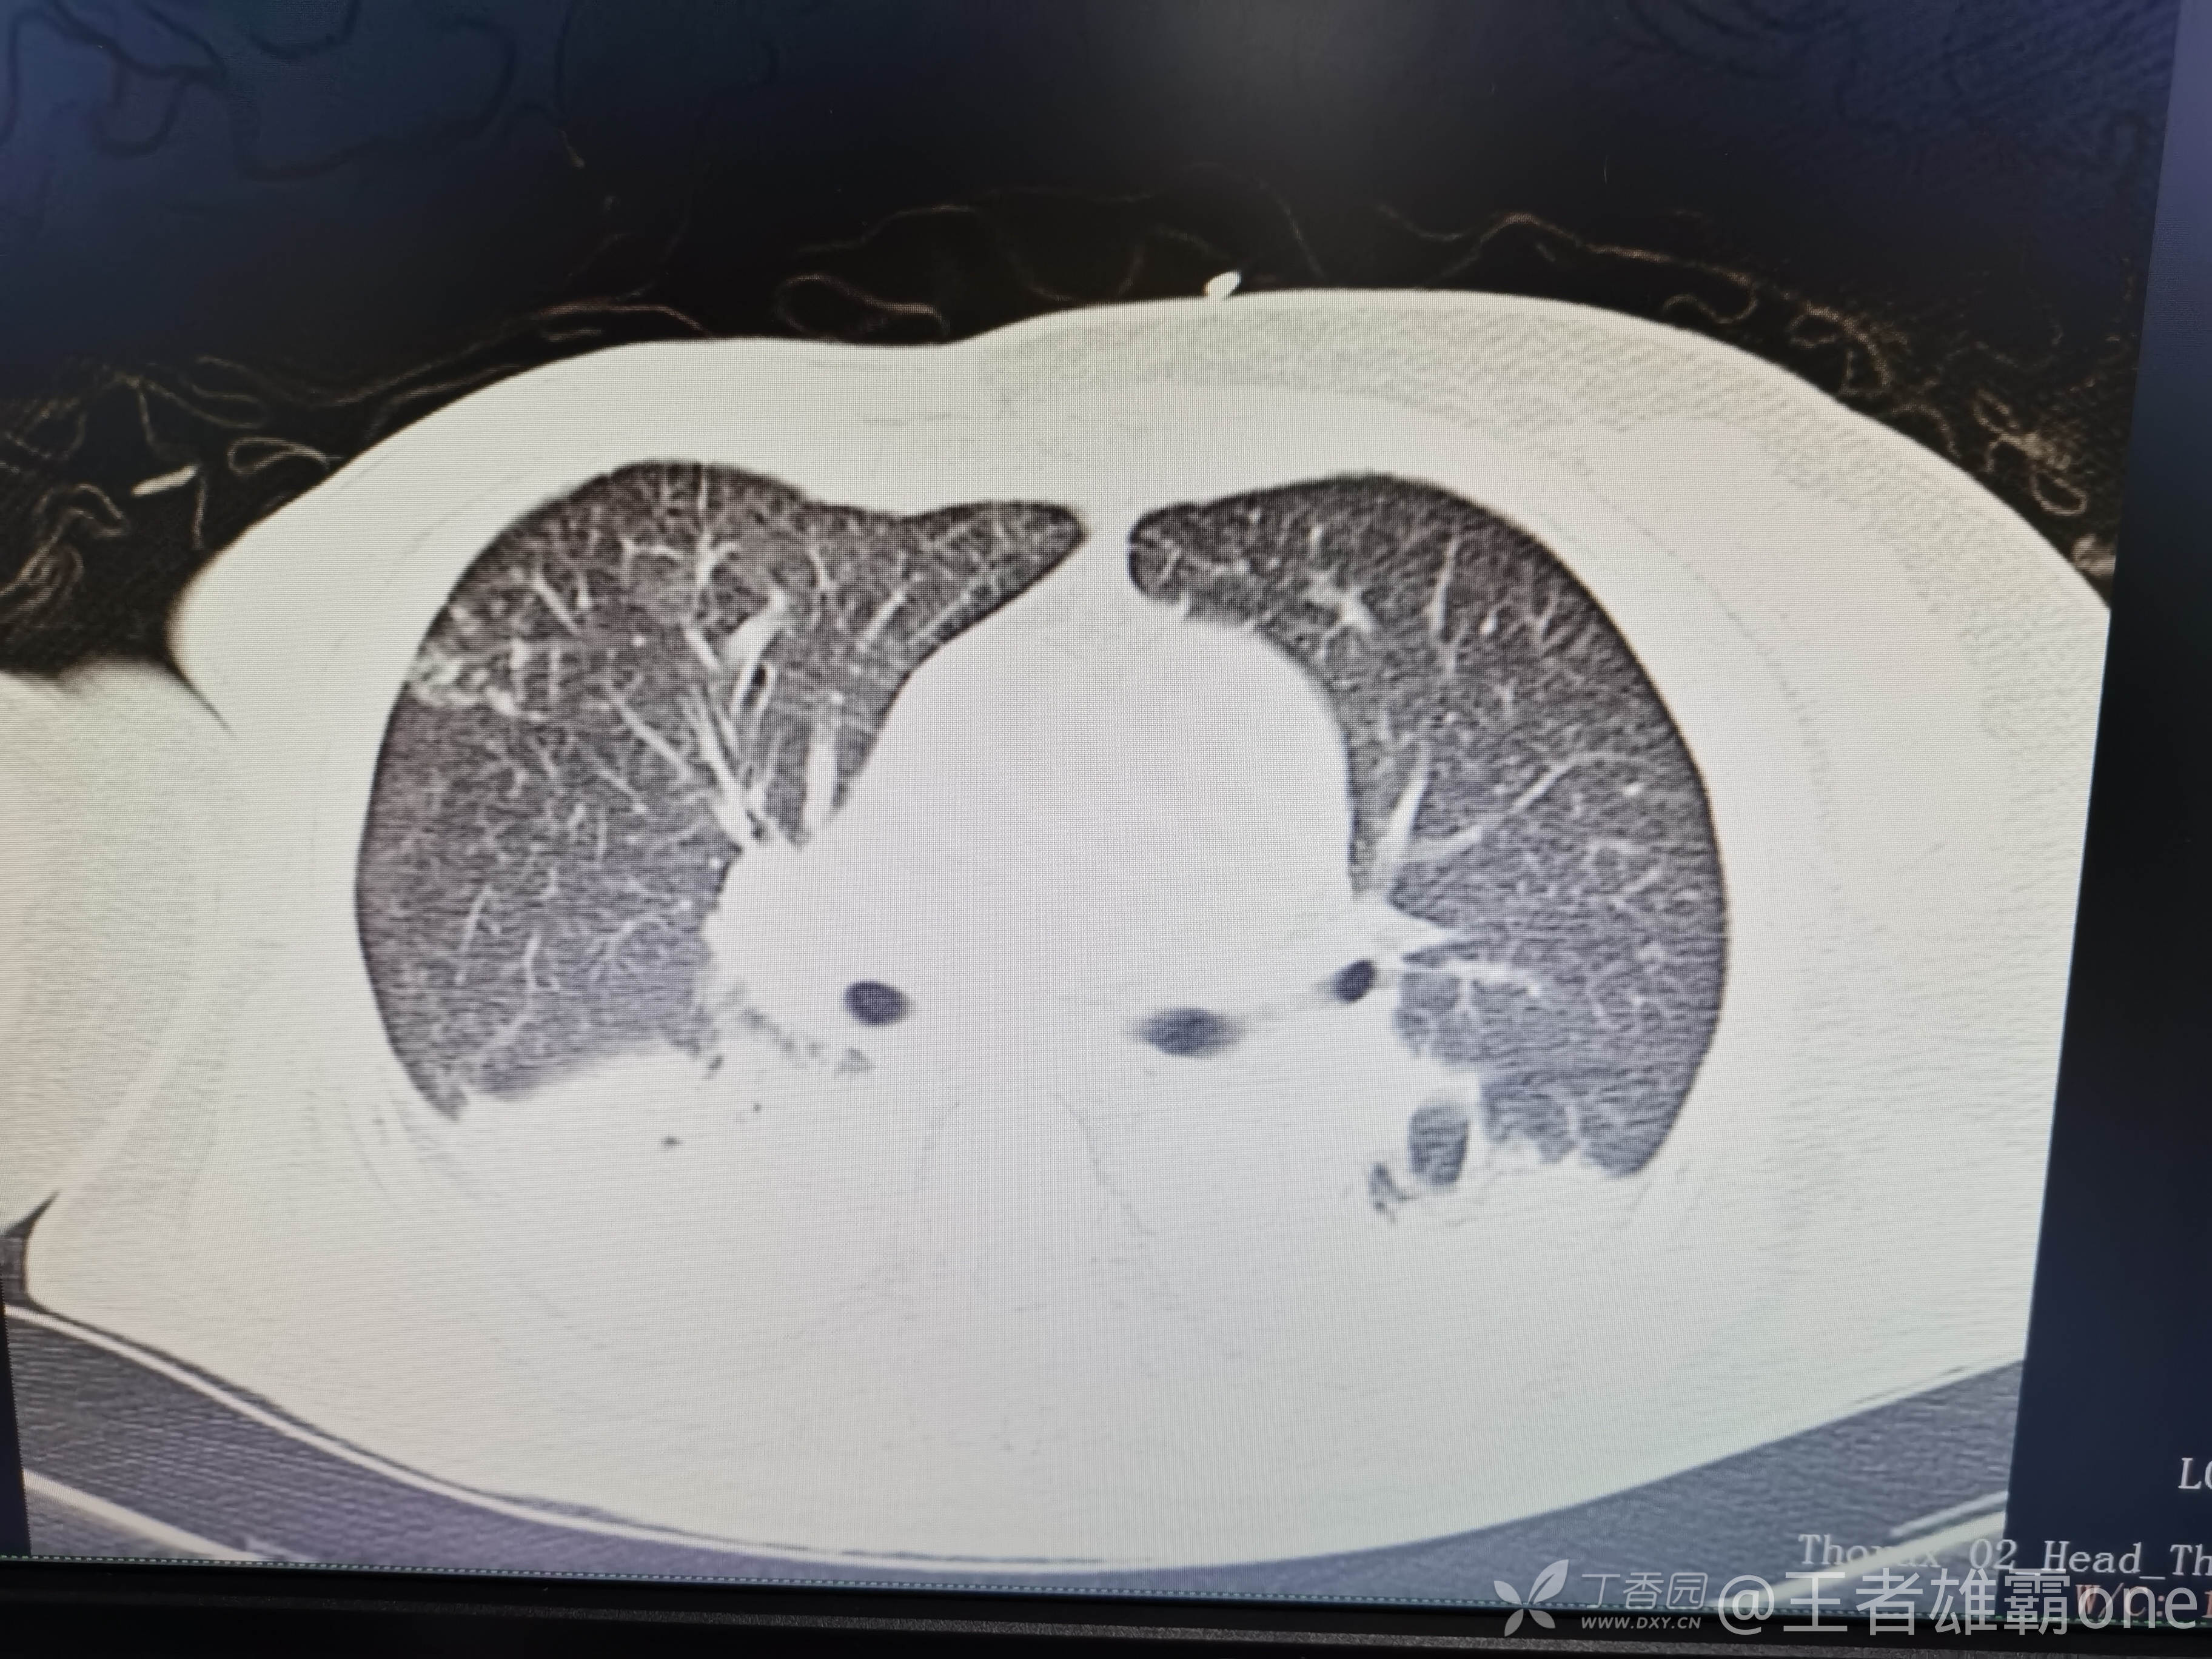

早上复查血常规:血红蛋白100g/L,白细胞11.1×109/L,血小板29×109/L。凝血功能:APTT37.9s,纤维蛋白原3.01g/L,凝血酶时间18.6s,D二聚体21530ug/L。生化:白蛋白36.2g/L,胆红素指标正常,谷丙56U/L,总胆红素38mmol/L,直接胆红素12.1mmol/L,谷草57U/L,肌酐91.1ummol/L,尿素13.97mmol/L,超敏C反应蛋白142.1mg/L。降钙素原17.70ng/ml。脑钠肽前体2164pg/ml。复查胸部CT:

那么问题来了,出现呼吸衰竭气管插管的病因是?请大家讨论分析!